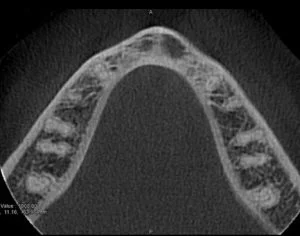

A CBCT was taken after a negative cold test indicated a necrotic tooth. When the CBCT was taken, we could clearly see that the abscess had completely perforated the labial bone at the apex of #24 and was close to doing so on #25.

As we investigated more deeply, we identified another critical piece of information that would affect our treatment plan: a second canal on #24.